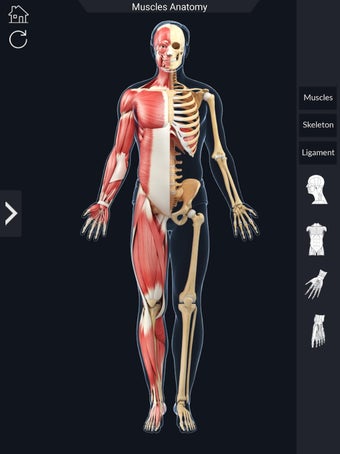

Den mest omfattande mobilappen som finns i världen för att studera muskelanatomi, som låter dig rotera 360°, zooma och flytta kameran runt en mycket realistisk 3D-modell.

Det finns många verktyg tillgängliga för varje muskel, inklusive:

- Rotera 360°.

- Zooma in och ut.